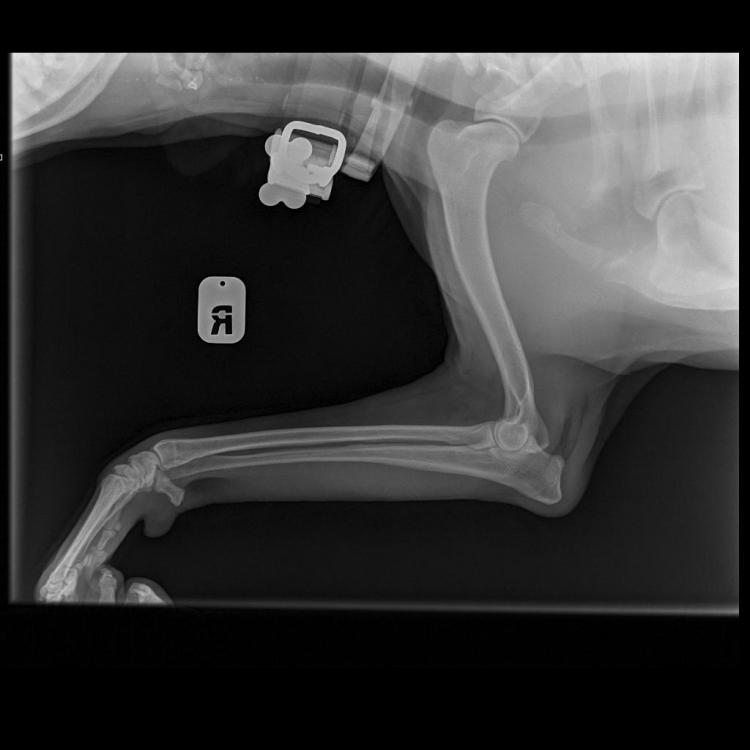

Яся&Лина&Лора Опубликовано 4 июня, 2020 Опубликовано 4 июня, 2020 Теперь все по порядку. Друзья, спасибо за терпение и выдержку! Писала на бегу. И, конечно же, спасибо за поддержку! В общем, Никуня нас немножко сегодня испугала, если честно. Поэтому побежали не раздумывая, выяснять что случилось с лапой. Как понимаете, боишься уже всего! В клинике нас встретил давно знакомый и совсем не страшный доктор Климухин И.Н. Очень внимательно и долго нас осматривал и щупал. Потом уже в конце приема сказал, что Никуся невероятно терпеливая девочка, молчит и терпит до последнего, даже никаких звуков не издаёт. Потом мы сделали 3 рентгеновских снимка и сдали кровь: общий и б/х (для контроля перед назначением обезболивающих). Кровь сдавали и температуру мерили с настоящим голдячим достоинством! Ну, правда... немножко случилась экспресс-линька.... Мне кажется, в Нике осталась вся клиника! Доктор нам отзвонился по анализам очень быстро. Анализы у нас прекрасные! Ура! За исключением повышенных лейкоцитов. Поэтому нужен контроль на фоне лечения через несколько дней. По рентгену криминала тоже нет никакого. По результату осмотра, есть небольшие проблемки с суставами, но ничего критичного. При этом, однозначно есть хромота на правую лапку, а реагирует при осмотре и левая тоже. Предположили, что, возможно, Никуся неудачно кувырнулась дома или оступилась?! Последнее время дожди и мы никуда не выезжали. Дома Никуся на диван залазит крайне редко. Внизу травмироваться вроде как негде?! Гуляет она всегда с огромным удовольствием. Возможно, на улице неудачно рванула вперед. Но, слава Богу! Ничего не порвала! И не вывихнула! В итоге доктор нам назначил Превикокс на 5 дней. В воскресенье ждет нас на контрольный осмотр, чтоб оценить динамику и надо будет повторить общий анализ крови, посмотреть лейкоциты. Счастью не было предела, волшебное слово «домой»! За все страдания получила немного вкуснях. «Где тут вкусняхи дают?» «Ням ням» «А мы уже домой?! Правда?!» «Тогда можно и расслабится!» «Поехали уже! Че стоим?!» 7